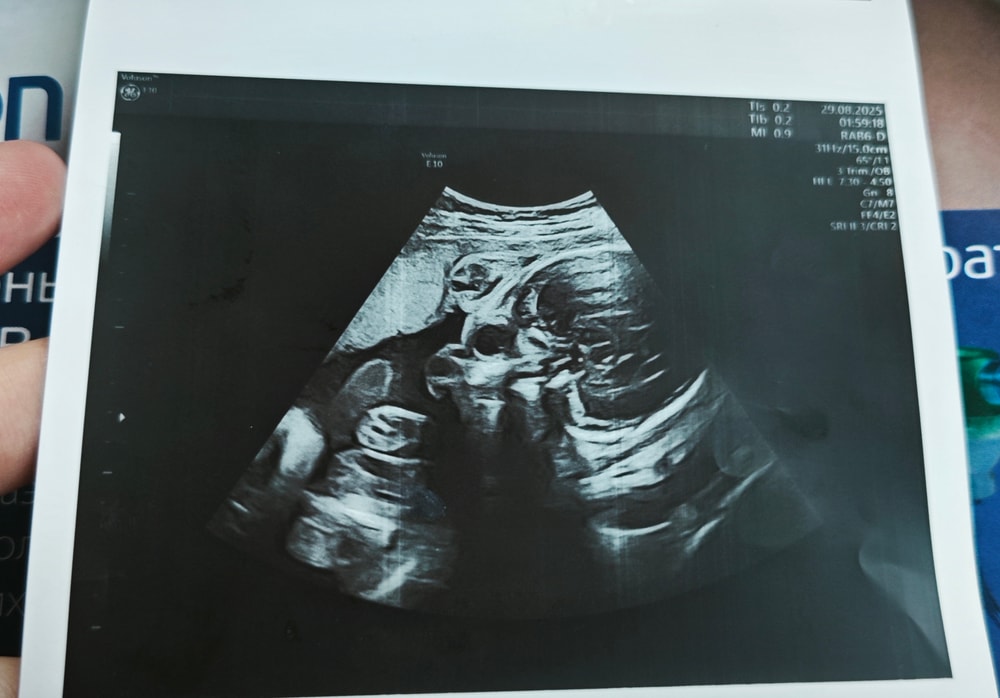

Фото с УЗИ 28 недель

Сходила в частную клинику на УЗИ в 28 недель, сказали, что всё хорошо ттт, и дали фото. И вот когда я уже вышла с клиники и увидела фото, я вообще ничего не поняла. Это вроде голова, но вообще непонятно что где и выглядит жутковато...

Анастасия , ну а что вы хотели от 2d узи? У вас все ок, видны глазницы. Лобные доли, нос. Сходите на цветное 3d, там черты лица увидите.